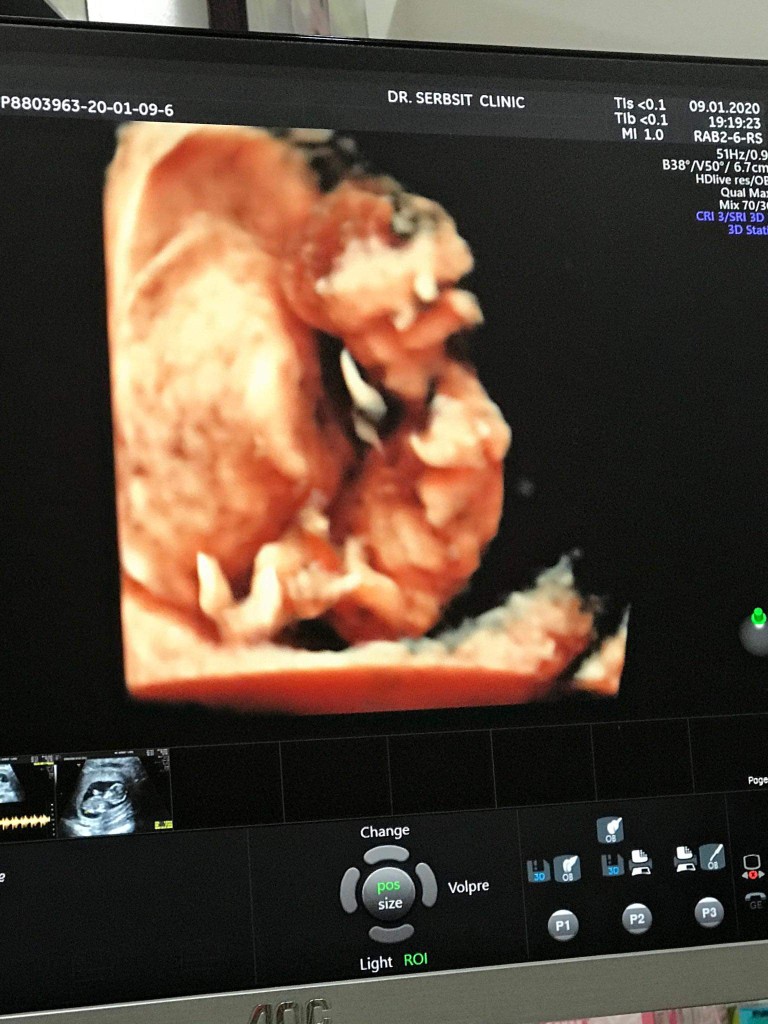

ตอน13w เพศชาย

พอมีมั้ยค่ะ😂